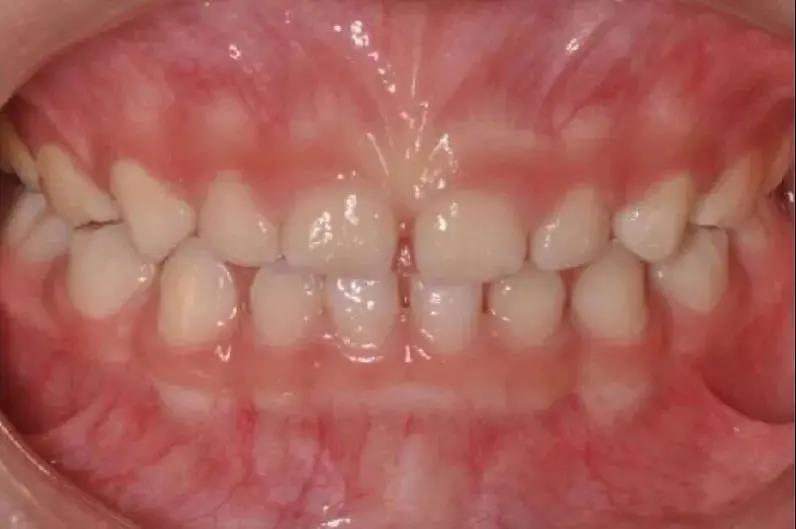

如發(fā)現(xiàn)孩子上下頜骨位置不佳

比如有明顯“齙牙”,應(yīng)盡早矯治

錯合畸形不僅影響孩子的口腔健康

還會影響面容,

進而影響孩子的心理健康。

早期矯治可以充分利用兒童的頜骨發(fā)育潛能

調(diào)整頜骨的生長平衡及牙弓發(fā)育

因此齙牙還是要盡早診治哦